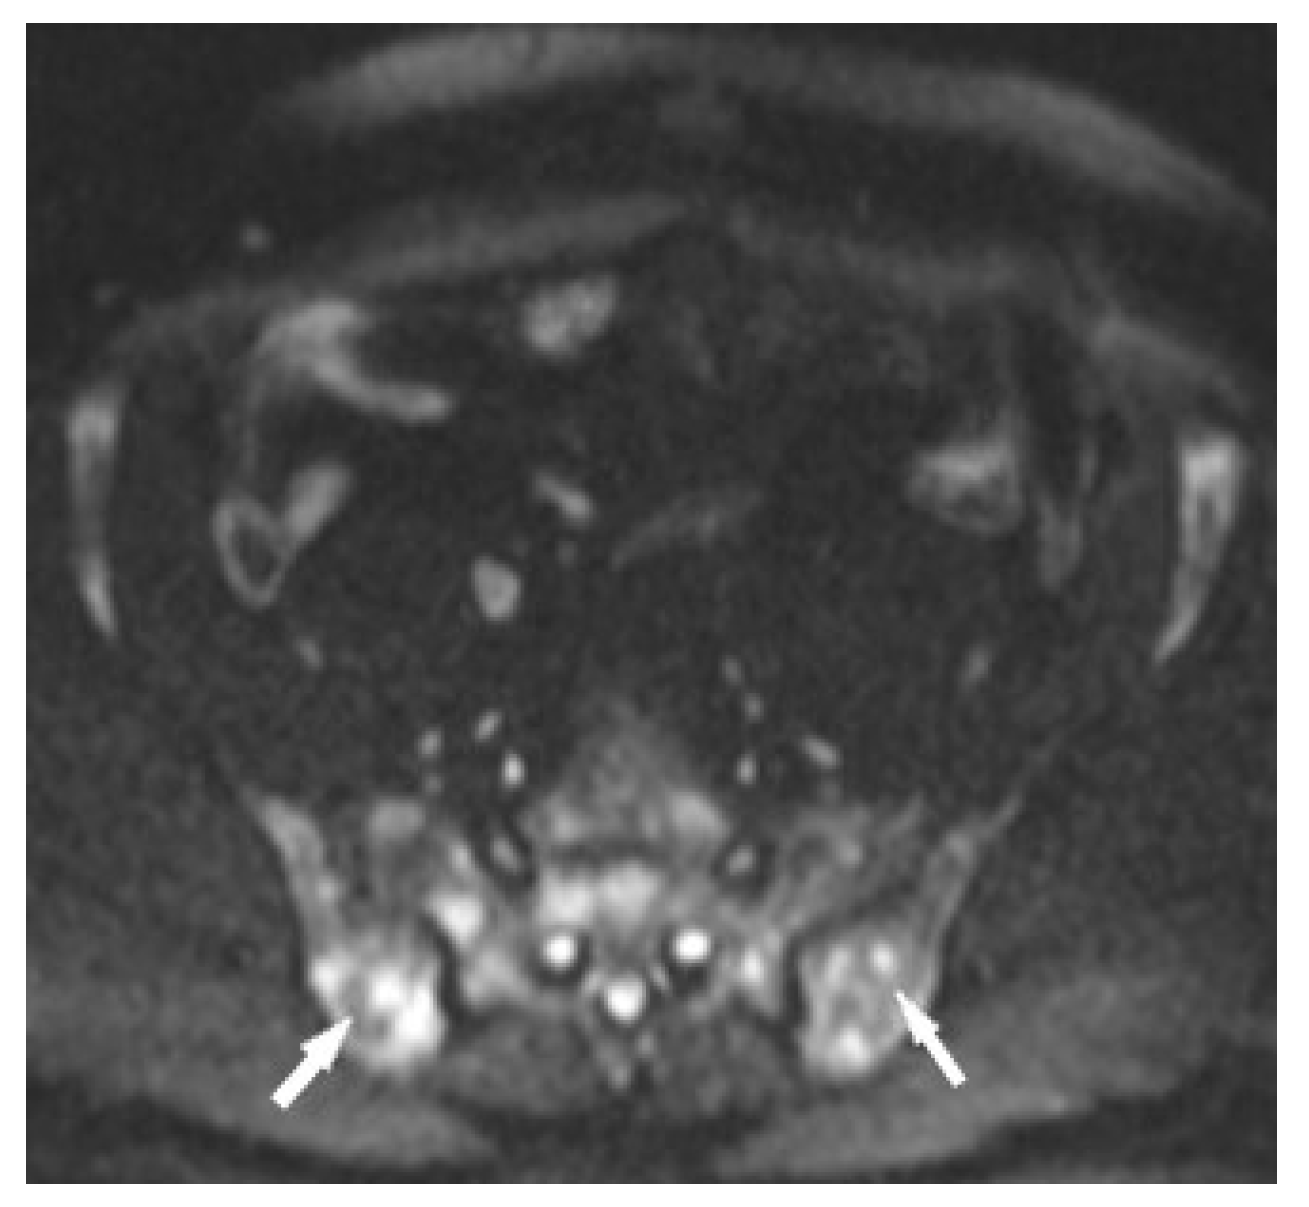

Figure 10. MRI of the pelvis, Diffusion-Weighted Imaging (DWI). Multiple bone marrow lesions with restricted diffusion (white arrows).

The specificity of MR imaging may be improved by diffusion-weighted imaging (Figure 10). Conte et al. pointed out that the Apparent Diffusion Coefficient (ADC) value of marrow sarcoidosis foci is lower compared to the ADC value of metastases, usually less than 700 µm2/s [21]. This study used DWI/ADC data from the whole-body MRI examination, but it seems that even with examinations limited to a single anatomical region it makes sense to include diffusion-weighted imaging as a part of the protocol. The authors suggest using diffusion images including other routine MR imaging sequences, which may avoid the patient’s administration of contrast. However, this does not change the clinical practice rules, that the suspicious lesion should be verified by histopathological analysis.